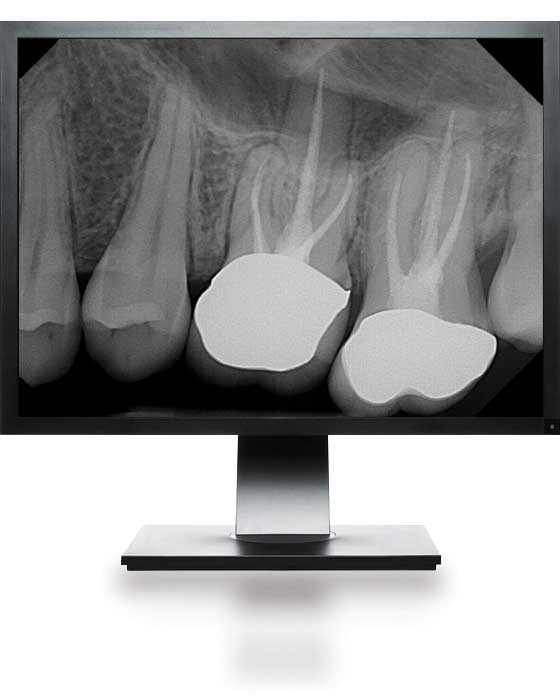

Applying our Dental Digital Radiography in Your Practice